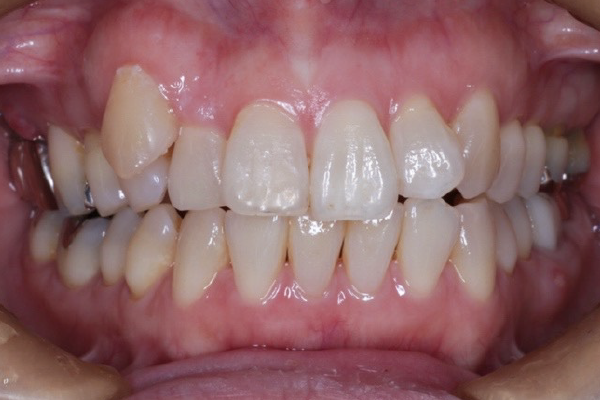

矯正治療前

50代女性のAさん(札幌市在住)

犬歯は外側にあり八重歯になっていました。ずっと歯並びは気になっていましたがなかなか機会がなく矯正治療はできませんでした。

前歯で物を咬めなく、下顎の状態が不安定でどこで咬んでいいかわからないことも悩みでした。

40代くらいから歯のトラブルが増えこのままでは歯がなくなってしまうと思い矯正治療をする決断をしました。